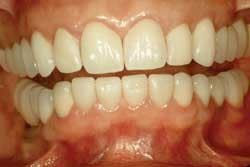

The excess cement is removed with a Bard Parker 12B scalpel blade. Minimal polishing is done with Sof-Lex™ Extra Thin Superfine Discs (3M ESPE) and Flexibuffs™ with Porcelize polishing paste (Cosmedent). The remaining veneers are seated in pairs following the same protocol (Fig. 9).

These steps have worked well for me in my practice. The halogen curing lights have withstood the clinical tests of time. Time will tell if the LED curing lights, with shorter curing times, will be as successful. While some dentists may feel comfortable seating multiple veneers at one time, my concern is improper seating and marginal adaptation that may be affected by tight interproximal contacts, drifting of the veneers, or both. By seating two veneers at a time, the clinician can make certain the restorations are completely seated the first time, reducing the likelihood of costly and timely replacements. I usually schedule approximately 15 to 20 minutes per veneer, depending on the patient. For example, if it is a maxillary, lingual-wrap veneer cemented with the Tack & Wave technique and using an LED curing light, it takes less time. The majority of time is spent trying in the veneers and preparing for the actual cementation.

With proper preparation design and cementation techniques, dentists can provide patients with one of the best-fitting, longest-lasting, esthetic porcelain restorations available. Profitability often can be measured by a satisfied patient’s smile and time-saving procedures.